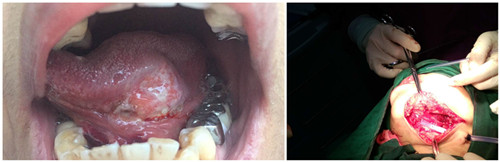

患者吴XX,女性,泉州籍,59岁,发现舌根一肿物并溃烂5月余,就诊我院耳鼻咽喉头颈外科。患者于舌根背面见一3.0X2.5cm大小肿物,肿物表面溃烂。 入院后进行了术前检查,肿物活检示:“舌高分化鳞状细胞癌”,彩超提示:“颏下及颌下多发淋巴结,余检查未见无异常”。经过详细周密的手术方案的制定,决定给患者实施“预防性气管切开+舌根恶性肿瘤切除+舌骨上淋巴结廓清+颈部淋巴结廓清+颊部带蒂粘膜瓣转移修复”。

患者气管插管全麻成功后,常规消毒铺巾,行预防性气管切开并重新更换麻醉插管,沿舌肿瘤边缘1.5cm切缘用强生超声刀切除肿瘤,肿物及切缘组织送冰冻病理检查。分离舌神经并加以保护,检查无肿瘤残留,冰冻病理回示:肿物高分化鳞状细胞癌,切缘均阴性。常规行舌骨上淋巴廓清术和颈部I区、II区淋巴廓清术,取颊部带蒂粘膜瓣修复口底无死腔,术中出血50ml,手术顺利,术后患者带气管套管安返病房。